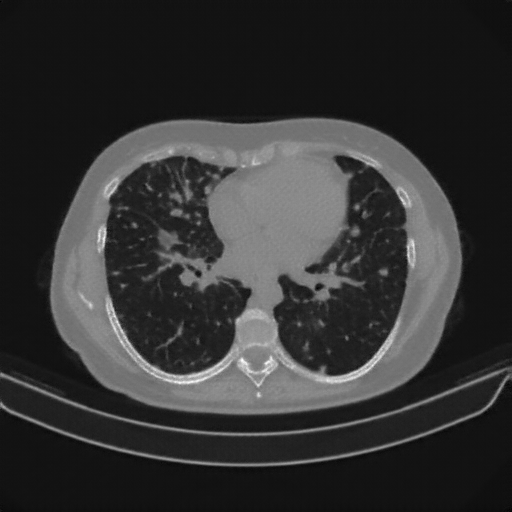

Reconstructed NATIVE CT scan (cycle consistency)

No window - Raw intensity values

Lung window (WL -600, WW 1500 β†’ Low βˆ’1350, High +150)

Mediastinum window (WL 40, WW 400 β†’ Low βˆ’160, High +240)